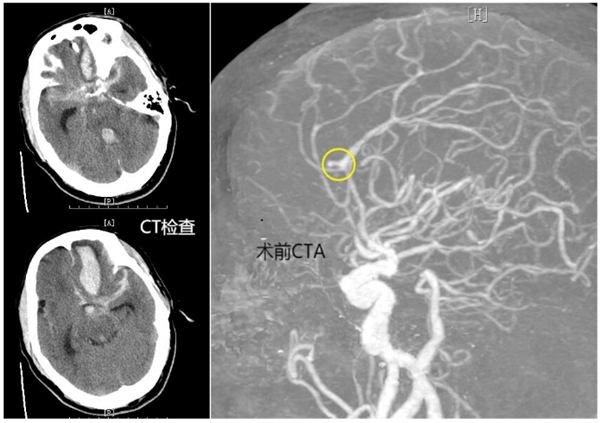

患者岑先生突發(fā)神志不清、呼之不應(yīng)。恩平市120急救中心快速將患者從當(dāng)?shù)匦l(wèi)生院轉(zhuǎn)至恩平市人民醫(yī)院開(kāi)展進(jìn)一步救治,并提前開(kāi)通生命綠色通道,完善初步CT檢查,并收入ICU。根據(jù)患者病程及CT結(jié)果,恩平市人民醫(yī)院神經(jīng)外科診斷為顱內(nèi)動(dòng)脈瘤破裂出血。

時(shí)間就是生命,恩平市人民醫(yī)院立即啟動(dòng)多學(xué)科聯(lián)合診療應(yīng)急處置預(yù)案,一方面由ICU快速行氣管插管、呼吸機(jī)輔助呼吸、降顱壓等治療。同時(shí),聯(lián)合放射科、醫(yī)學(xué)檢驗(yàn)科、麻醉手術(shù)科、導(dǎo)管室等科室開(kāi)放快速診療通道。急查頭頸部CTA提示:左側(cè)大腦前動(dòng)脈瘤、左額葉大量腦出血破入腦室、蛛網(wǎng)膜下腔出血。

由于患者顱內(nèi)動(dòng)脈瘤破裂出血量極大,已陷入深度昏迷,Hunt-HessⅤ級(jí),病情危重,時(shí)間緊迫。醫(yī)生向患者家屬告知病情,并建議盡快手術(shù),將出血的動(dòng)脈瘤進(jìn)行栓塞,防止再度出血。